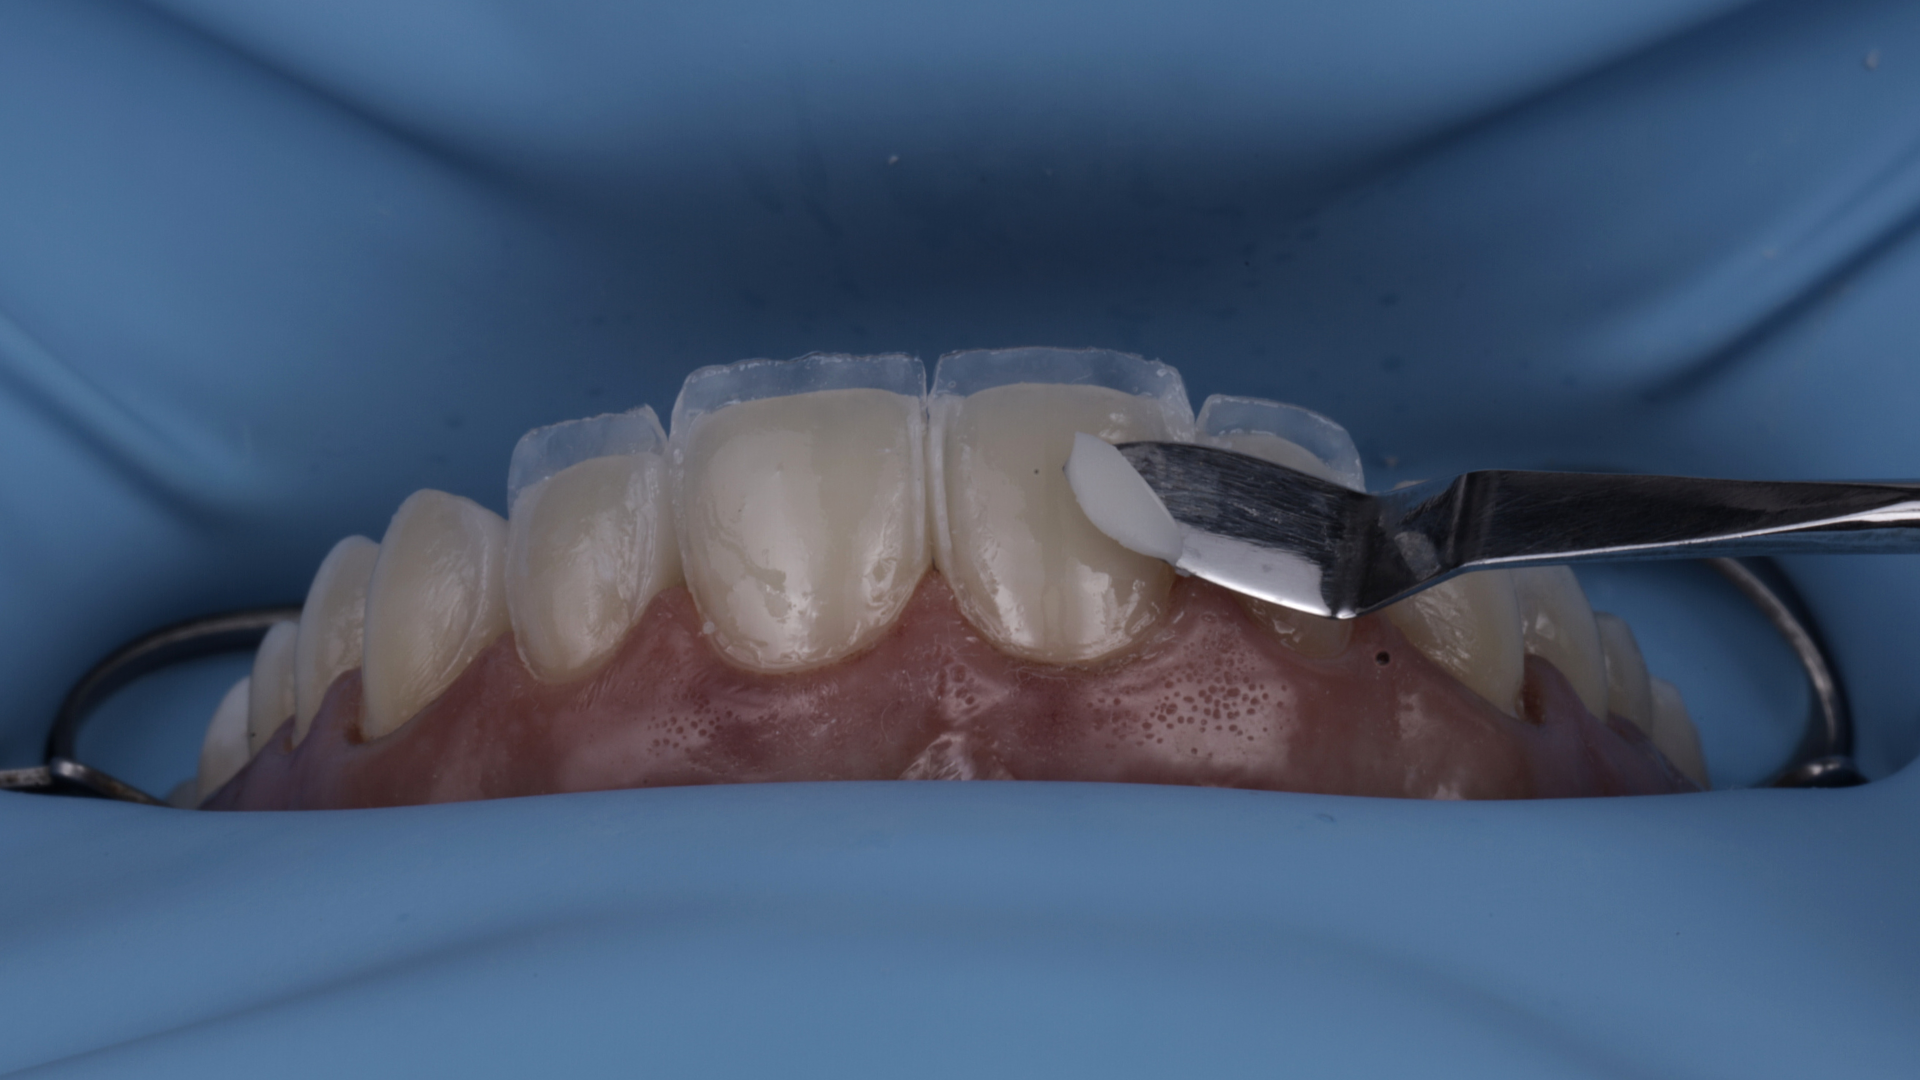

Full Veneers

Dictado por el Dr. Daniel Zabaleta, especialista en Rehabilitación Oral, Estética y Dentística con más de 20 años de experiencia y más de 19.000 casos clínicos exitosos.